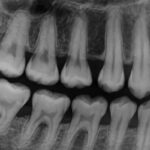

Gum disease starts as gingivitis (red, swollen, bleeding gums). If untreated, it can progress to periodontitis. Periodontitis causes pockets to form between teeth and gums, bone loss, loose teeth, and sometimes tooth loss. Common signs include bad breath, gum recession, bleeding when brushing, deep pockets, and shifting teeth. Early diagnosis improves outcomes.

Clinicians measure success with pocket depth, bleeding on probing, and imaging when needed. If pockets stay deep or infection returns, additional treatment or referral to a periodontist may be necessary. Long-term periodontal maintenance visits every 3–4 months are often required to prevent recurrence.